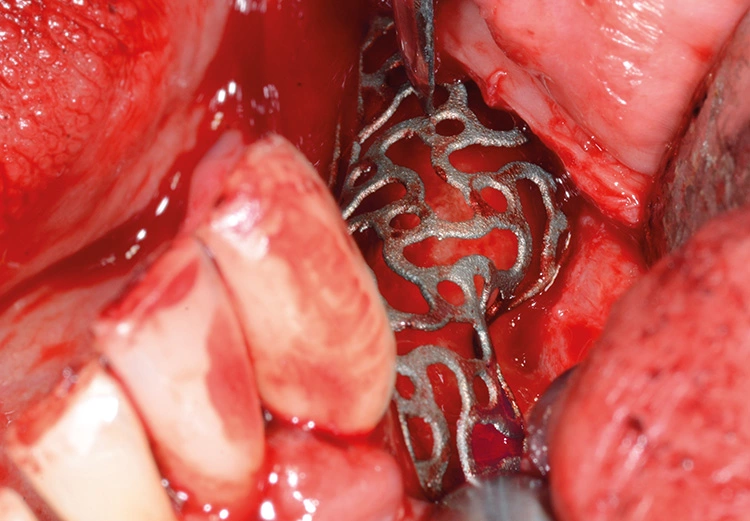

Bei der digitalen Planung des Gitters wurde dieser Aspekt besonders berücksichtigt und zudem auf die Lage des Foramen mentale speziell geachtet. Das Gitter wurde im Austrittsbereich ausgespart, um eine Traumatisierung zu vermeiden (Abb. 4-19).

Trotz der schlechten, hart- und weichgewebigen Grundvoraussetzungen konnte der Kieferkamm zufriedenstellend rekonstruiert werden. Die Augmentation des kombinierten, horizontalen und vertikalen Defekts mit Yxoss CBR®, Geistlich Bio-Oss®, Geistlich Bio-Gide®, autologem Knochen und PRF ermöglichte die Implantation mit hoher Primärstabilität in den rekonstruierten Bereich.